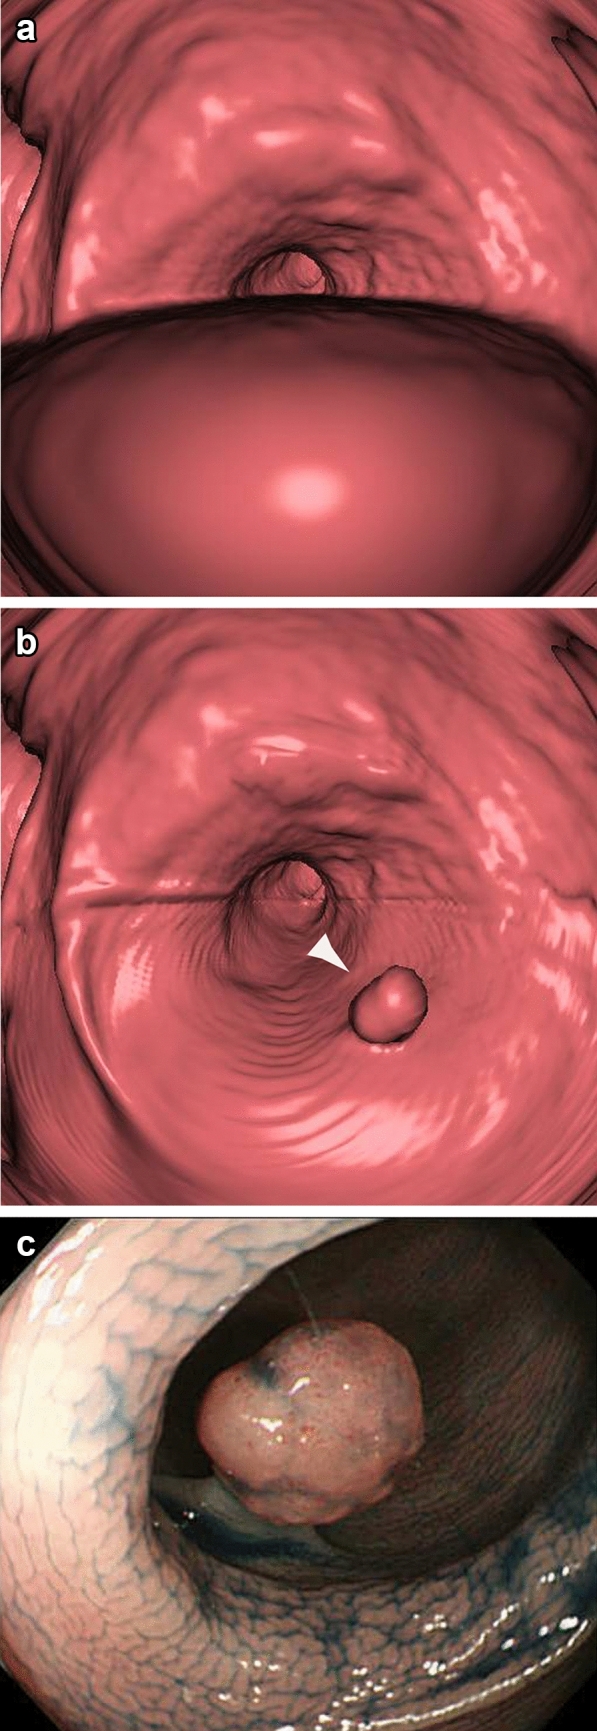

结直肠癌仍然是世界范围内死亡的主要原因,早期发现对于改善预后至关重要。CT结肠镜检查(CTC)已成为一种有前途的替代光学结肠镜检查大肠癌筛查。本文探讨了CTC在日本的发展潜力,重点关注质量控制、患者可接受性、并发症及其在筛查项目中的作用。CTC检测结直肠息肉具有较高的敏感性和特异性,对≥10 mm病变的诊断效果与结肠镜相当。粪便标记和双位置成像等技术可显著提高诊断准确性。然而,诊断结果的可变性强调了严格的解释培训和质量控制的必要性。美国放射学会建议至少对50例结肠镜检查证实的病例进行培训。尽管CTC有诸多优势,但由于医疗专业人员的认知度低、训练有素的放射科医生短缺以及缺乏支持使用CTC的具体指导方针,日本采用CTC的程度仍然有限。与结肠镜检查相比,CTC的非侵入性、更短的检查时间和更少的肠道准备要求,使患者对CTC的接受度很高。然而,并发症,如肠穿孔,虽然罕见,需要仔细的风险评估。虽然CTC在美国和欧洲已被认可用于筛查和诊断随访,但将其纳入日本的结直肠癌筛查指南对于扩大其应用至关重要。为了最大限度地发挥反恐的效益,必须努力使方法标准化,建立质量指标,并就降低死亡率和成本效益产生强有力的证据。

Colorectal cancer remains a leading cause of mortality worldwide, and early detection is essential for improving outcomes. CT colonography (CTC) has emerged as a promising alternative to optical colonoscopy for colorectal cancer screening. This article explores the potential of CTC in Japan, focusing on quality control, patient acceptability, complications, and its role in screening programs. CTC has demonstrated high sensitivity and specificity for detecting colorectal polyps, with its diagnostic performance comparable to colonoscopy for lesions ≥ 10 mm. Techniques such as fecal tagging and dual-position imaging significantly enhance diagnostic accuracy. However, the variability in diagnostic outcomes underscores the need for rigorous interpretation training and quality control. The American College of Radiology recommends training with at least 50 cases verified by colonoscopy. Despite its advantages, the adoption of CTC in Japan remains limited due to low awareness among medical professionals, a shortage of trained radiologists, and the absence of specific guidelines endorsing its use. Patient acceptability for CTC is high due to its non-invasive nature, shorter examination time, and reduced bowel preparation requirements compared to colonoscopy. Nonetheless, complications such as bowel perforation, albeit rare, necessitate careful risk assessment. While CTC has been recognized in the U.S. and Europe for screening and diagnostic follow-up, its integration into Japan's colorectal cancer screening guidelines is crucial to expand its utilization. To maximize the benefits of CTC, efforts must focus on standardizing methodologies, establishing quality indicators, and generating robust evidence on mortality reduction and cost-effectiveness.